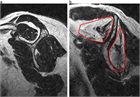

1. 外傷歴のはっきりしない腱板断裂や無症候性腱板断裂が存在する(推奨度2)